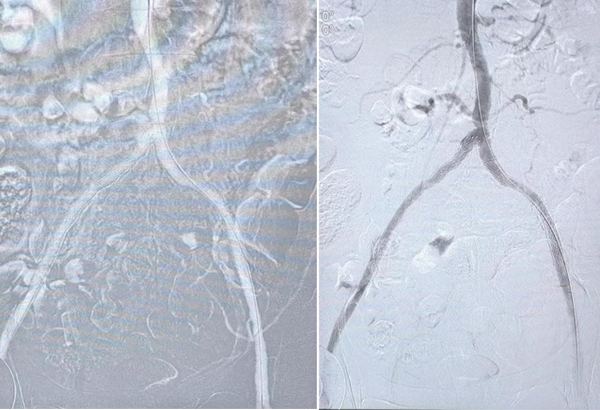

血管造影图

手术,取左肱动脉为入路,入长鞘至降主动脉,造影见腹主动脉及双侧髂动脉未见血流通过,捻转导丝通过左侧髂动脉闭塞段,进行球囊扩张后可见少量血流通过,置入溶栓导管并留置。术后,给予足量肝素钠抗凝、尿激酶溶栓治疗,监测凝血指标,等待下一次手术治疗。

两天后,为患者行对侧手术治疗,撤除溶栓导管,沿长鞘造影可见腹主动脉及左侧髂动脉溶栓效果良好,未见明显血栓残留,同样方式行右侧髂动脉置管溶栓,术后治疗同上。

经过两天后的积极治疗,王颖主任带领其团队成员再次为患者行介入手术治疗,术中造影可见腹主动脉及双侧髂动脉血流明显改善,溶栓治疗效果显著,但局部仍有明显狭窄,于狭窄处给予支架植入,术毕。